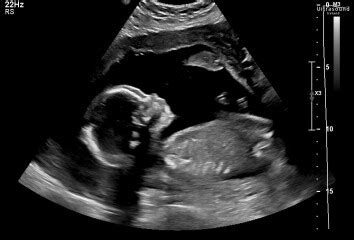

Hey everyone! So, you’re heading in for that big 20-week ultrasound , also known as the anatomy scan. It’s a super exciting milestone, right? This is when we get to see your little one in all their glory, checking to make sure everything is developing as it should be. But let’s be real, guys, it’s also totally normal to feel a little bit of anxiety. We often hear folks asking, “ What are the common bad news findings at a 20-week scan? ” It’s a valid question, and we’re here to break it down in a way that’s easy to understand, so you can feel more prepared and less stressed. Remember, the vast majority of these scans come back with fantastic news – a healthy baby! But understanding potential concerns can help demystify the process and empower you with knowledge.

The 20-week anatomy scan is a really important part of your prenatal journey. It’s way more than just a fun peek at your baby’s features; it’s a detailed examination where trained sonographers and radiologists meticulously check about a dozen or so different organs and structures of your developing baby. They’re looking at the brain, heart (including all four chambers and major vessels), lungs, kidneys, stomach, bladder, spine, and all four limbs, to name a few. They measure everything to ensure your baby is growing at the expected rate and that all the physical components are forming correctly. It’s this detailed look that allows us to identify many potential issues early on. When we talk about “bad news,” it’s crucial to remember that these findings are often things that can be managed, treated, or simply monitored. Early detection is key, and that’s precisely what this scan provides. It’s a tool for reassurance and, if needed, for planning. The technicians are highly skilled and trained to spot even subtle variations. They’re not just looking for major problems; they’re assessing growth, proportions, and the overall development of each system. Think of it as a thorough check-up for your baby before they even arrive. The goal is to ensure everything is on track for a healthy delivery and a healthy start to life. While the word “abnormality” can sound scary, it’s important to understand that many findings are minor and resolve on their own, while others may require further investigation or intervention after birth. The scan provides valuable information that helps your healthcare team provide the best possible care throughout your pregnancy and beyond. It’s a comprehensive assessment designed to give you peace of mind and to ensure that any potential concerns are identified as early as possible.